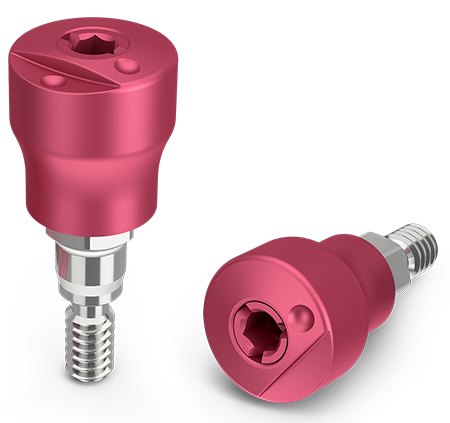

Encode Emergence Features

Heal Naturally. Impress Easily.

Easy, efficient and proven Encode technology with contemporary emergence profile designs, intuitive codes and pink matte appearance.

Eliminate the healing abutment and impression coping or scan body swapping process, while delivering soft tissue healing with natural emergence profile.

Available in various emergence profile diameters and heights (2.9, 3, 5, and 7-mm).